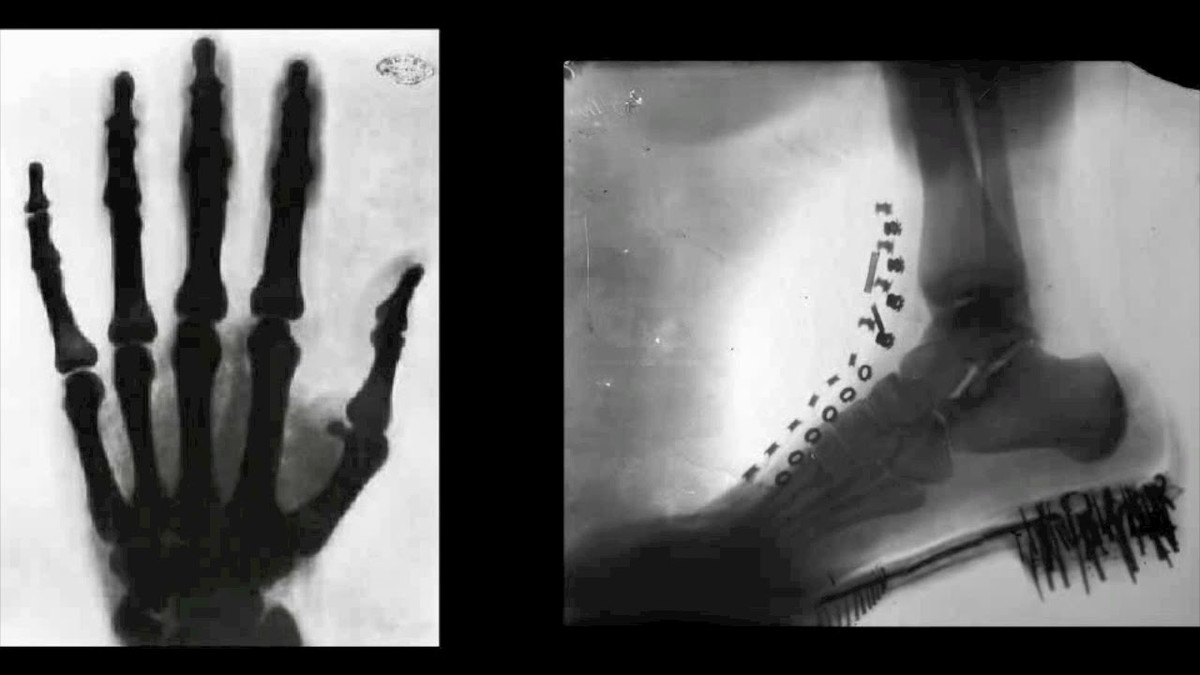

Nha khoa hoc Nikola Tesla co thuc su tu choi nhan giai Nobel?-Hinh-6

Nikola Tesla đã khám phá ra tia X từ rất sớm. Ảnh minh họa

Mặc dù Wilhelm Conrad Röntgen - nhà khoa học người Đức được ghi nhận là người đầu tiên khám phá ra tia X vào năm 1895, tuy nhiên, có bằng chứng cho thấy Nikola Tesla cũng đã khám phá ra tia X trước đó vài năm.

Ông đã thử nghiệm với bức xạ và chụp được một số hình ảnh tia X đầu tiên của cơ thể con người, mà ông gọi là shadowgraph. Bên cạnh đó, ông cũng là một trong các nhà khoa học đầu tiên có giả thuyết về sự gây hại của tia X.